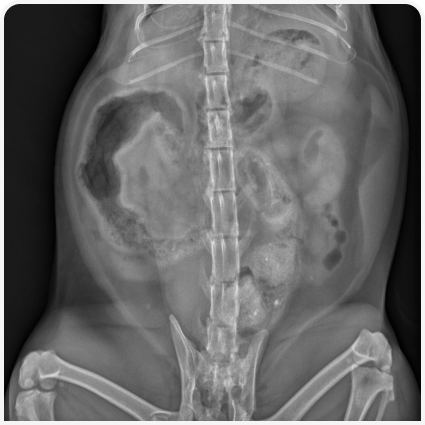

У кошек, страдающих запором, обычно удается транс­абдоминально пальпировать скопившийся в толстой кишке кал, но при тяжелом ожирении или в случае если животное проявляет беспокойство, это может оказаться непросто. Также могут появляться тошнота или признаки обезвоживания. Следует провести неврологическое обследование, включая пальпацию позвоночника, и офтальмологическое обследование, чтобы определить, является ли запор частью более обширного нервно-мышечного расстройства (например, вегетативной дисфункции, заболевания спинного мозга). Тщательное ректальное обследование под седацией или анестезией позволяет выявить каловые конкременты, объемные образования или инородные тела в заднем проходе, смещенные переломы таза, стриктуры прямой кишки, воспаление параанальных желез. Иногда у кошек в результате длительных фекальных тенезмов может образоваться грыжа промежности.

При необходимости проводят дополнительное обследование. Первой диагностической целью врача должно быть подтверждение запора и оценка его хронизации и тяжести, для чего обычно достаточно непосредственного обследования и рентгенографии, как описано выше. Учитывая, что идиопатический мегаколон и стеноз тазового канала составляют около 85% случаев (1), у большинства кошек при запорах обширное диагностическое обследование не требуется, но у отдельного пациента важно не пропустить поддающуюся лечению причину. Потенциальными показаниями для дальнейшего диагностического обследования служат неврологические нарушения (например, связанные с вегетативной дисфункцией), пальпируемые образования в брюшной полости или ректоанальной области, рентгенологически обнаруженные поражения брюшной полости / тазового канала, непропорциональная карликовость у молодых кошек (соответствует врожденному гипотиреозу) или другие признаки системного заболевания. К примерам иногда требующихся дополнительных тестов относятся определение гормонов щитовидной железы (т. е. общего Т4, свободного Т4, тиреотропного гормона) при подозрении на гипотиреоз, УЗИ органов брюшной полости при подозрении на объемные образования в стенке или вне просвета толстой кишки, рентгенография в поперечной плоскости при подозрении на заболевания позвоночника или объемные образования в полости таза, колоноскопия для выявления воспалительных поражений, ректоанальных стриктур или дивертикулов.